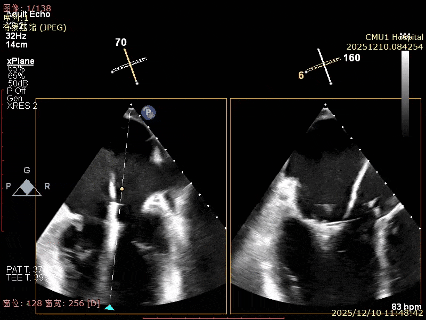

术后影像

最终结果3D-Zoom-color显示组织桥稳定,原脱垂区域前后叶对合部分的脱垂已消除,反流降至1+以下

夹子释放Bi-com切面显示残余反流情况

肺静脉收缩期逆流消失,频谱形态基本恢复正常

术后2D TTE:

术后TTE可见二尖瓣微量-轻度反流,三尖瓣反流明显改善降至中度